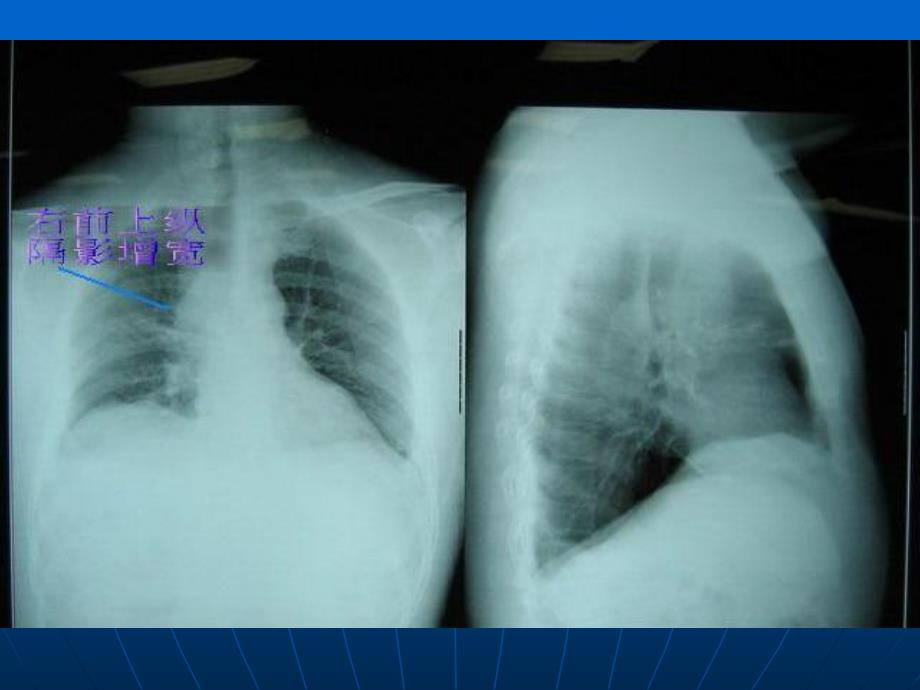

《肿瘤急症——上腔静脉综合症.ppt.ppt》由会员分享,可在线阅读,更多相关《肿瘤急症——上腔静脉综合症.ppt.ppt(27页珍藏版)》请在第壹文秘上搜索。